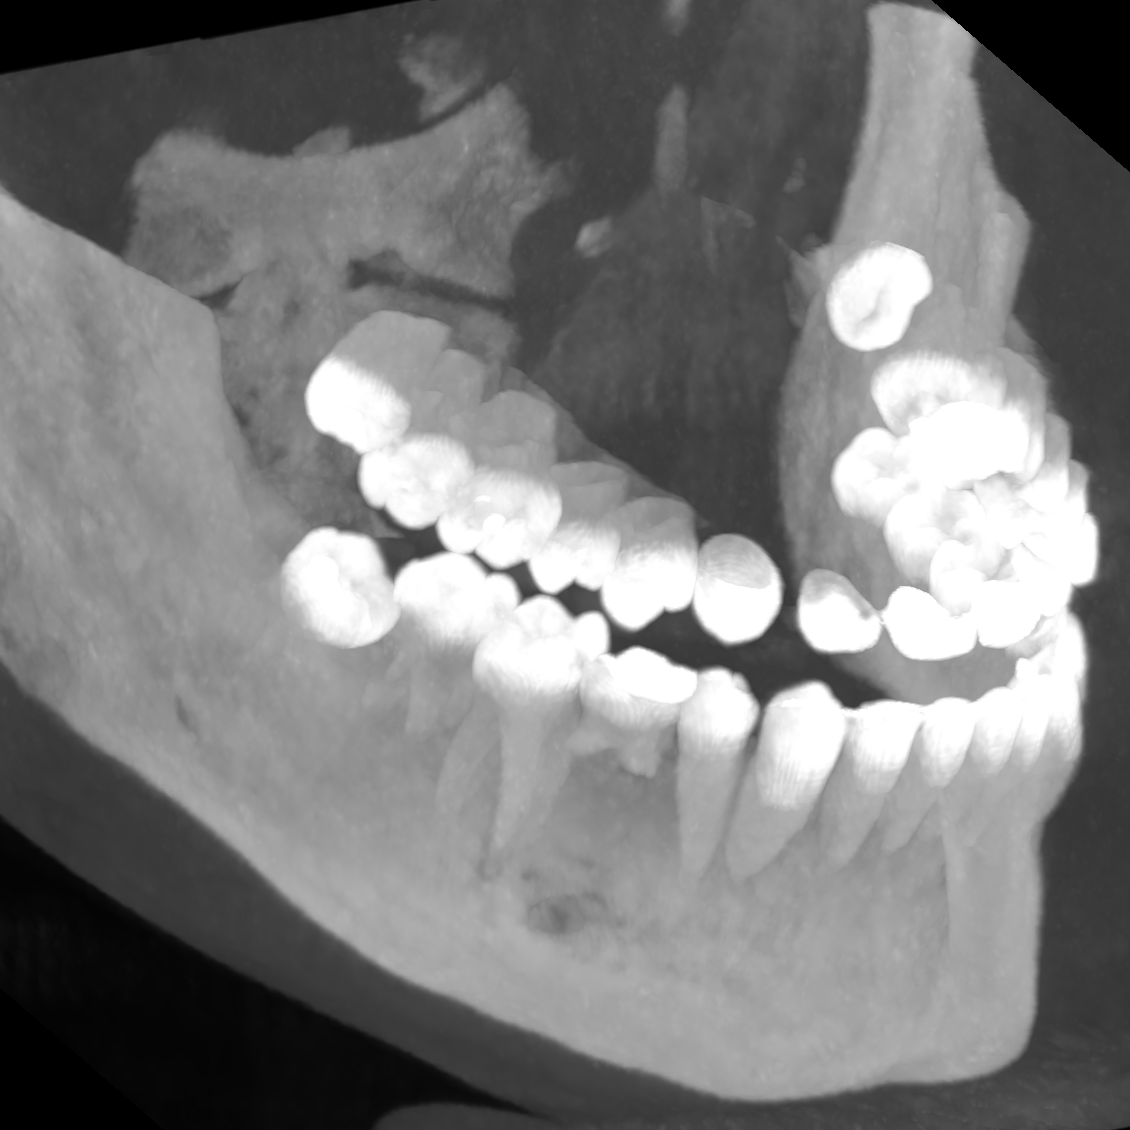

| ToothFairy[6, 5] | 3D | binary | 138 | Inferior Alveolar Canal |

We employ five public datasets featuring thin structures for validating the proposed Skeleton Recall Loss. The datasets span natural as well as medical images, covering a range of segmentation challenges, including both binary and multi-class segmentation problems in 2D as well as 3D contexts. An overview of the datasets can be found in Tab. 1. Among the three 2D datasets used in this study, the Digital Retinal Images for Vessel Extraction (DRIVE) dataset [32] was employed, focusing on retinal vessel segmentation. Additionally, structural inspection images designed for concrete crack segmentation (Cracks) [36] and aerial images of Massachusetts for road segmentation (Roads) [21] were included, highlighting the diversity of thin structures in natural and constructed environments. In the 3D domain, we incorporated two cutting-edge medical image segmentation challenge datasets. One of them was ToothFairy111https://toothfairy.grand-challenge.org/, which was a segmentation challenge on 3D Cone-Beam CTs [6, 5] featuring the inferior alveolar canal as the target structure. Additionally, the TopCoW222https://topcow23.grand-challenge.org/ dataset for topology-aware 3D segmentation of vessels in the Circle of Willis for CTA and MRA data [40] was utilized, encompassing binary as well as multi-class segmentation on 13 different subtypes of vessels. This diverse set of datasets enables a comprehensive evaluation of the proposed Skeleton Recall Loss, demonstrating generalizability of the method to a wide range of thin structure segmentation challenges in both 2D and 3D contexts.